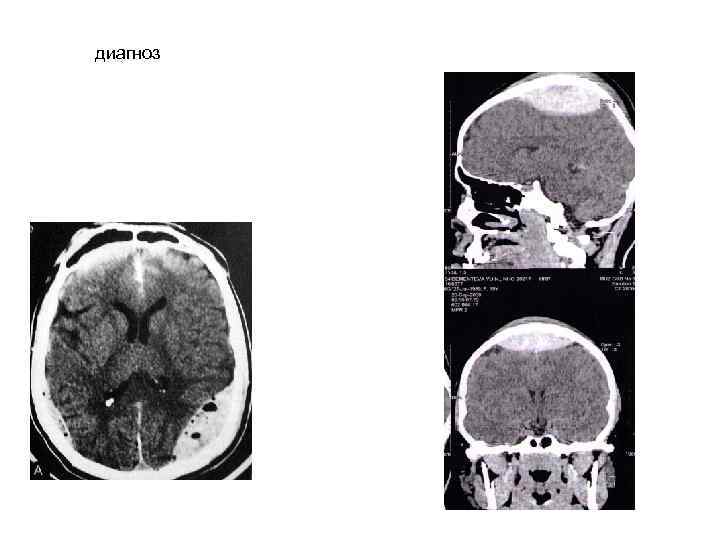

диагноз